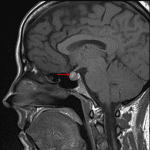

Age: 36

Sex: Female

Indication: Galactorrhea, hyperprolactinemia

- T1 hyperintense, T2 isointense rounded lesion along the superior margin of the pituitary gland measuring 9 x 8 x 6 mm

- Internal rounded area of T2 signal hypointensity measuring 3 mm in diameter

- No corresponding enhancement

- The lesion bulges into the suprasellar cistern but does not clearly contact the optic chiasm

Rathke cleft cyst